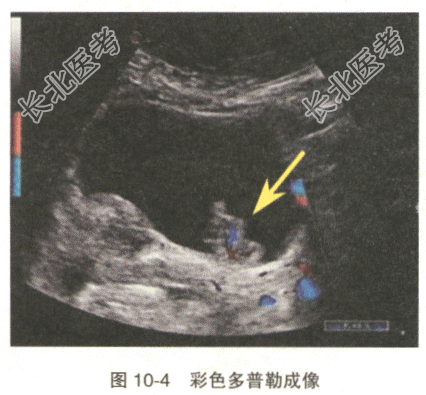

患者,女性,66岁。血尿腰痛1个月余,超声检查显示(图10-3):右肾中部低回声肿块,大小约32mm×22mm,膀胱右侧壁输尿管开口处探及一低回声,内见条状血流信号(图10-4),右侧输尿管开口处未见喷尿现象。